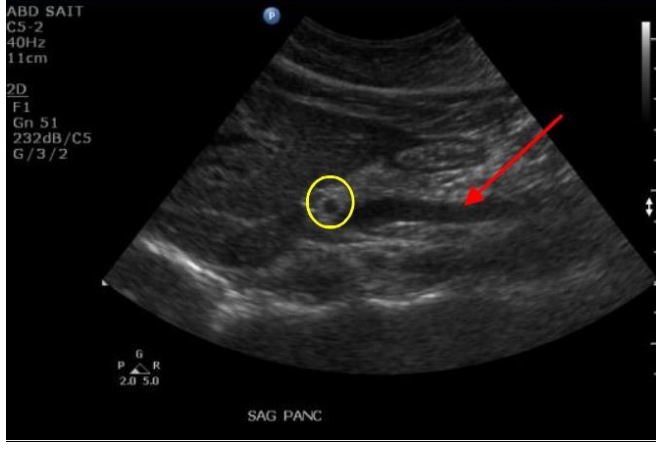

Q

Label the Red arrow and the yellow circle

A

Red arrow: SMV

Yellow circle: Splenic artery